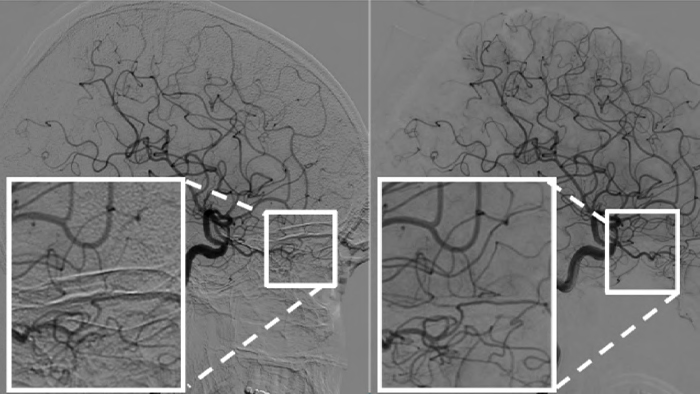

When you are monitoring AVMs over time, subtraction artifacts can disguise clinical information. Philips’ unique ClarityIQ automatic pixel shift helps remove information that may be misleading, in real-time and without user interaction.

During treatment, subtraction artifacts can obscure the direction liquid embolic agents are traveling. Using the automatic pixel shift in our ClarityIQ enables you to visualize the direction the liquid embolic agent is traveling and its arrival.